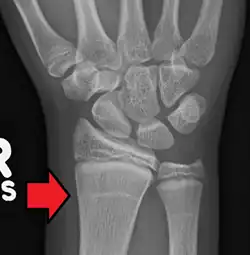

Les stries d'arrêt de croissance été décrites au début du XXe siècle par plusieurs auteurs : Ludloff (1903), Eliot (1927) et Harris (1933)[2]. Correspondant à un excès de minéralisation osseuse, les lignes de Harris apparaissent sous la forme d'une ligne dense transversale au sein d'un os long en radiographie conventionnelle[2].

Pour être considérée comme une authentique ligne de Harris, certains auteurs recommandent une largeur minimale par rapport à l'os avec différents seuils proposés (25, 30 voire 50 % selon les études)[2],[3]. Il existe cependant une variabilité inter-observateur dans la détection radiographique de ces lignes et certains auteurs, afin d'obtenir une meilleure reproductibilité ont développé des logiciels de détection[1],[2].